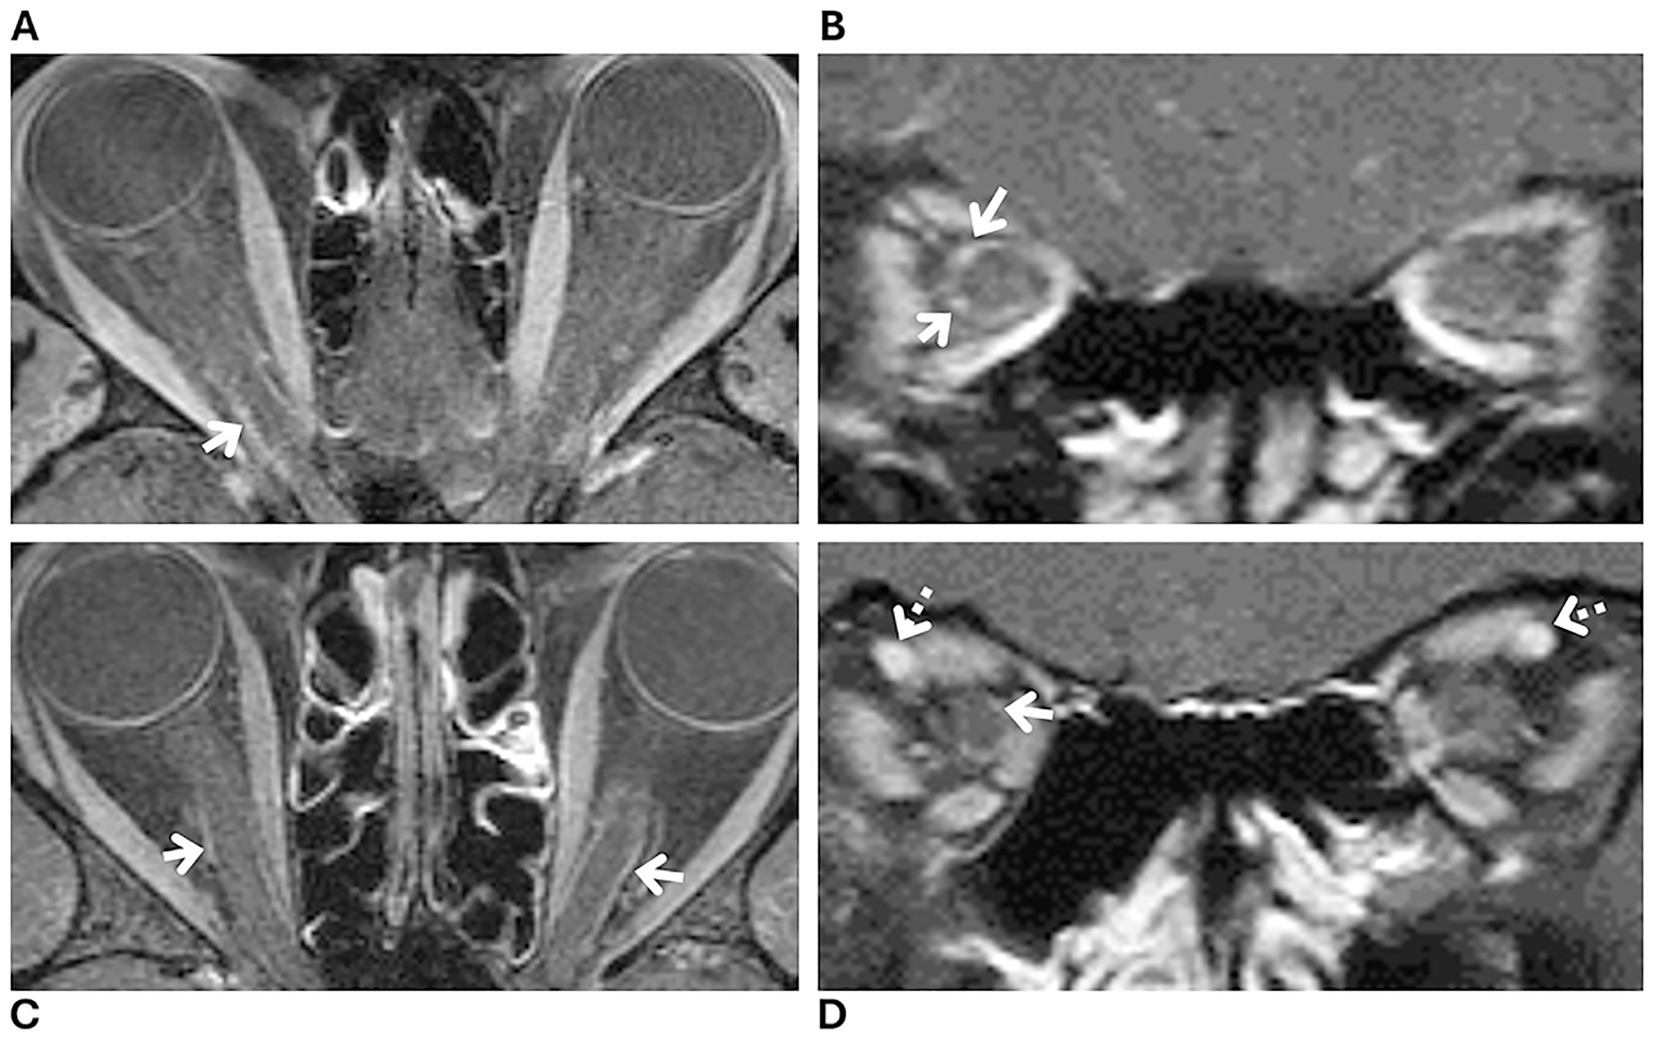

Introduction: Optic nerve sheath enhancement (ONSE) is a radiologic sign commonly associated with a diagnosis of optic perineuritis. However, recent studies have reported this radiologic sign in patients with idiopathic intracranial hypertension (IIH). The presence of ONSE in patients with IIH may lead to optic perineuritis diagnosis in excess. We evaluated the prevalence of ONSE in patients with a new diagnosis of IIH. Methods: Retrospective study of consecutive patients who presented to the emergency department of our quaternary care center with a suspected intracranial pressure disorder between June 15, 2023 and July 1, 2024. Patients who received a new diagnosis of IIH fulfilling the 2013 revised diagnostic criteria and who underwent orbital magnetic resonance imaging (MRI) with fat-suppressed contrast-enhanced sequences were included. An expert neuroradiologist evaluated all orbital MRIs for the presence of ONSE. Results: Forty-three patients with a new diagnosis of IIH were included (mean age, 31±7 years; 100% women; 72% Black, 20 % White, and 8 % other). Of these 43 patients, three were categorized as having suggested ONSE versus blood vessels. The remaining 40 patients were categorized as having no ONSE. Discussion: ONSE is a radiologic sign that may occur in approximately 7 % of patients with newly diagnosed IIH. However, the distinction between mild ONSE and blood vessels surrounding or within the optic nerve sheath is challenging. A location at the distal infraorbital portion of the optic nerve sheath and a corkscrew appearance are suggestive of a vascular etiology. Awareness of this radiologic sign in patients with IIH is important to avoid optic perineuritis diagnosis in excess.